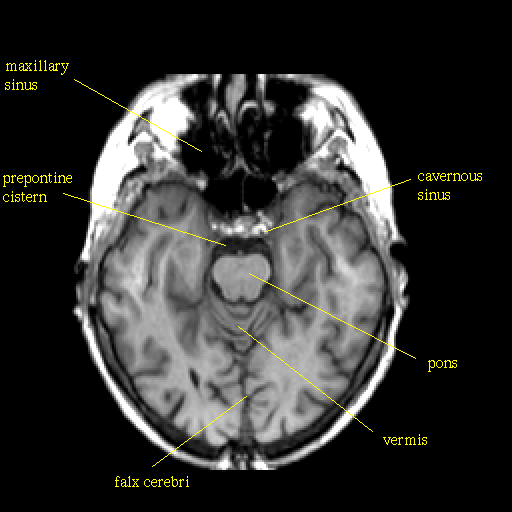

T1-weighted structural MR: Slice 19

Slice 19